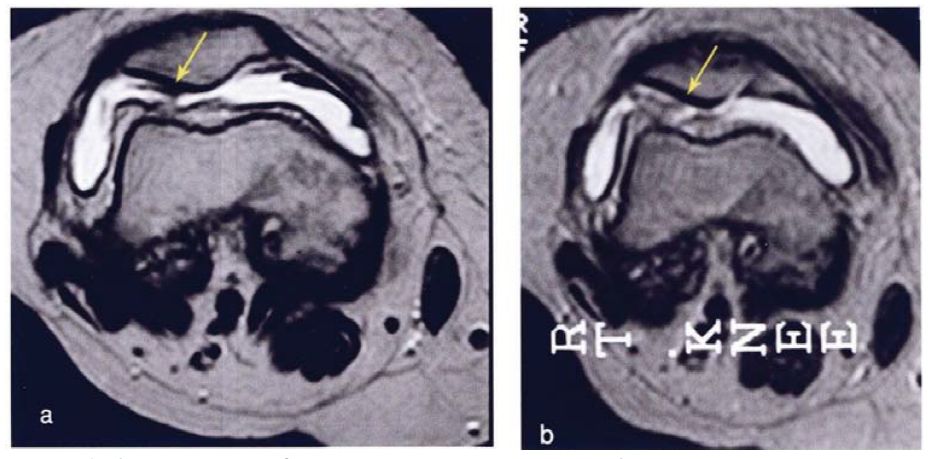

评价指标: MRI | VAS评分 | WOMAC评分 | 步行距离

治疗结果:关节内注射脐带干细胞6个月后,疼痛、功能状态和步行距离均提高。6名治疗组中3名患者在治疗前后的MRI比较可以看出,该治疗对于改善软骨厚度,修复组织延伸超过软骨下骨,以及减少软骨下骨的水肿是非常显著的。

上图a示意治疗前软骨,b为治疗后6个月软骨,箭头所示为软骨修复位置。